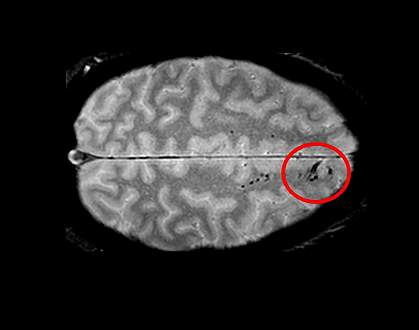

Researchers have wondered if a type of tiny abnormality seen on MRI in some people with TBI may be associated with long-term disability. Some scientists proposed that these tiny spots or lines, called traumatic microbleeds (TMBs), are caused by the tearing of nerve cells in the brain. Others suggested that they represent damage to blood vessels. The relationship between TMBs and long-term disability has been unclear.

About 31% of all participants had TMBs on their MRI scans. These abnormalities were not confined to people with severe brain injuries: 27% of people with mild TBI and 47% of people with moderate TBI had evidence of TMBs.

People with TMBs immediately after their injury were twice as likely to report disability 30 and 90 days afterwards than people with no TMBs. Microbleeds were associated with disability independent of other known risk factors, including severity of the overall brain injury and damage seen on CT scans.

Imaging and dissection of the donated brain found evidence of damage to the blood vessels at the sites of TMBs. The researchers did not see nerve cell damage. Because only one brain was available for tissue studies, the researchers could not rule out nerve cell damage playing a role in some TMBs.